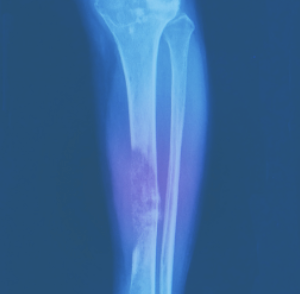

- 이미징 테스트: X-레이, CT 스캔, MRI 스캔 및 PET 스캔과 같은 이미징 테스트를 사용하여 신체 내부의 이미지를 생성하고 육종의 크기, 위치 및 단계를 결정하는 데 도움을 줄 수 있습니다.

CT(컴퓨터 단층 촬영) 스캔은 신체의 상세한 단면 이미지를 생성하기 위해 X-선과 컴퓨터 기술을 사용하는 일종의 영상 검사입니다. CT 스캔은 일반적으로 육종을 진단하고 종양의 크기, 위치 및 단계를 평가하는 데 사용됩니다. CT 스캔은 또한 육종이 신체의 다른 부분으로 퍼졌는지 확인하는 데 도움이 될 수 있습니다.

CT 스캔과 같은 영상 검사는 신체 내부의 사진만 제공할 수 있으며 육종 진단을 확정할 수 없다는 점을 명심하는 것이 중요합니다. 일반적으로 진단을 확인하고 육종 유형을 결정하기 위해 생검이 필요합니다.